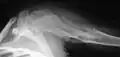

X-ray showing enchondromas localized in the humerus of a 37-year-old patient affected with Ollier disease -

Enchondromas localized in the upper part of the humerus of the same patient

The disease consists of the growth multiple enchondromas which usually develop in early childhood. The growth of these enchondromas usually stops after skeletal maturation.[4] The affected extremity is shortened (asymmetric dwarfism) and sometimes bowed due to epiphyseal fusion anomalies. Bone lesions generally present as cellular during childhood and become more solitary over time. People with Ollier disease are prone to breaking bones (fractures) and normally have swollen, aching limbs. However, many cases of solitary enchondromata go unnoticed due to lack of symptoms. Enchondromas are commonly found in the phalanges, metacarpal, and metatarsal bones in patients of Ollier disease due to the affinity of enchondromas to long tubular bones such as the femur and humerus. A unilateral distribution of bone lesions is usually observed but bilateral distributions or a singular extremity can occur as well. Approximately a third of the cases show some form of physical deformities of bowing or abnormal limb lengthening.